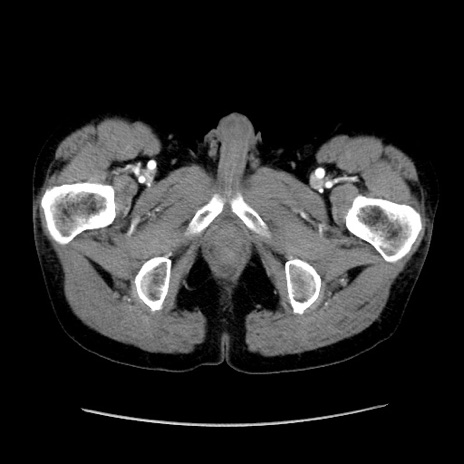

冠状断像